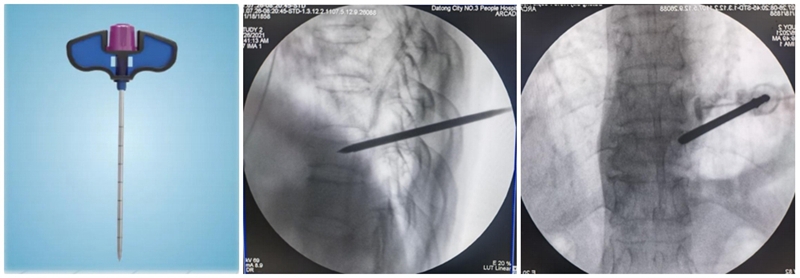

(1)定位与穿刺:透视下确定伤椎椎弓根外缘上1/3 入路点及伤椎上终板或下终板方向并做好标记。由于穿刺容错率高,穿刺针(4. 2 mm)不用过度内倾,不必苛求针尖在椎体内侧壁、后壁位置,穿刺针从椎弓根外缘沿椎弓根方向缓慢穿刺入椎体即可,针尖务必穿刺入椎体后1/3。